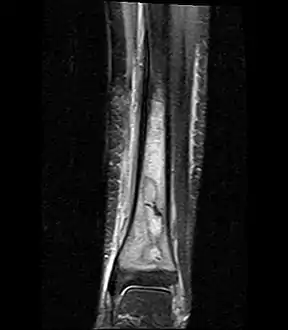

A Brodie abscess is a subacute osteomyelitis, which may persist for years before progressing to a chronic, frank osteomyelitis. Classically, this may present after progression to a draining abscess extending from the tibia out through the skin. Occasionally acute osteomyelitis may be contained to a localized area and walled off by fibrous and granulation tissue.

Oval, elliptical, or serpentine radiolucency usually greater than 1 cm surrounded by a heavily reactive sclerosis, granulation tissue, and a nidus often less than 1 cm. The margins often appear scalloped on radiograph. Brodie's abscess is best visualized using computed tomography (CT) scan. Associated atrophy of soft tissue near the site of infection and shortening of the affected bone. Osteoblastoma may be a classic sign for Brodie's abscess.